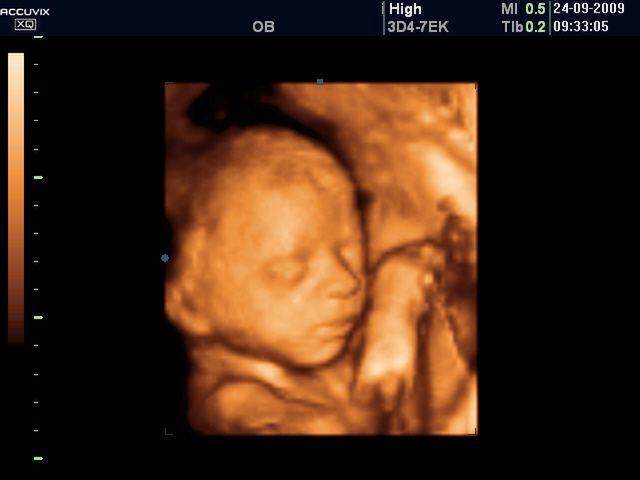

Płód w 26 tygodniu ciąży (zdjęcia 3D)

Pod skórą dziecka gromadzi się coraz więcej tkanki tłuszczowej